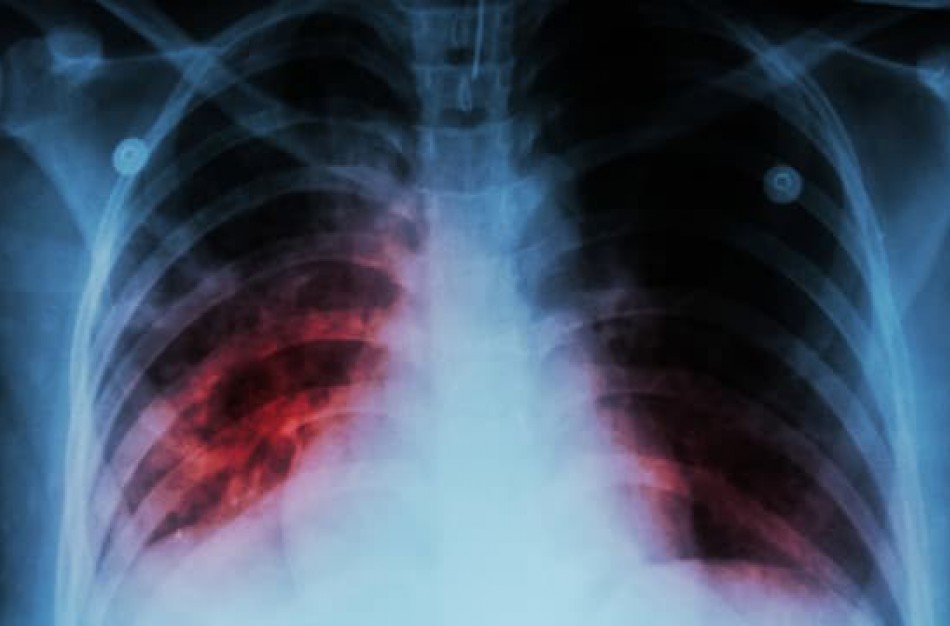

Nacionalinio visuomenės sveikatos centro Jonavos skyriaus specialistai informuoja, kad šiais metais Jonavoje užregistruota 20 naujai susirgusių atvira plaučių tuberkulioze atvejų. Visi susirgusieji yra suaugę asmenys, iš kurių 14 vyrų ir 6 moterys, gyvenantys kaime (10) ir mieste (10).

Pirmieji požymiai, kurie leidžia įtarti ligą, yra kosulys, silpnumas, prakaitavimas nakties metu, nesmarkus karščiavimas, kartais skausmas krūtinėje ar padidėję limfmazgiai. Jeigu kosulys nepraeina daugiau kaip per tris savaites, būtina pasikonsultuoti su gydytoju. Pasitikrinti ypač svarbu tiems, kurių šeimos nariai serga arba anksčiau sirgo tuberkulioze ar kurie turėjo sąlytį su sergančiu tuberkulioze asmeniu. Rizika užsikrėsti padidėja, jei bendraujama ilgai ir intensyviai su sergančiuoju atvira plaučių tuberkulioze, ypač prastai vėdinamose patalpose.

Ankstyvas ligos išaiškinimas ir gydymas yra pagrindinės priemonės, galinčios ne tik išgelbėti gyvybę, bet taip pat – užkirsti kelią infekcijos plitimui visuomenėje.